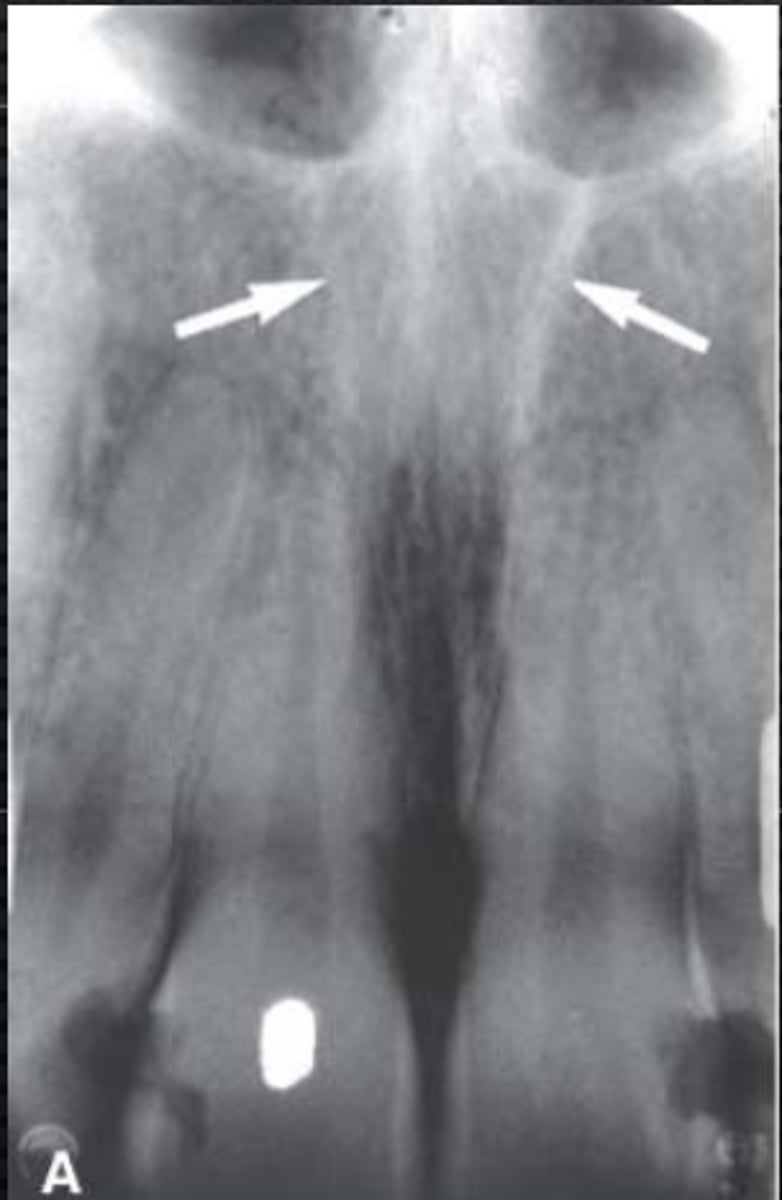

New cards

Nasopalatine canal

Identify the straight, radiopaque lines indicated by the white arrows.

<p>Identify the straight, radiopaque lines indicated by the white arrows.</p>

Superior foramina of the nasopalatine duct

Name the two round radiolucencies indicated.

<p>Name the two round radiolucencies indicated.</p>